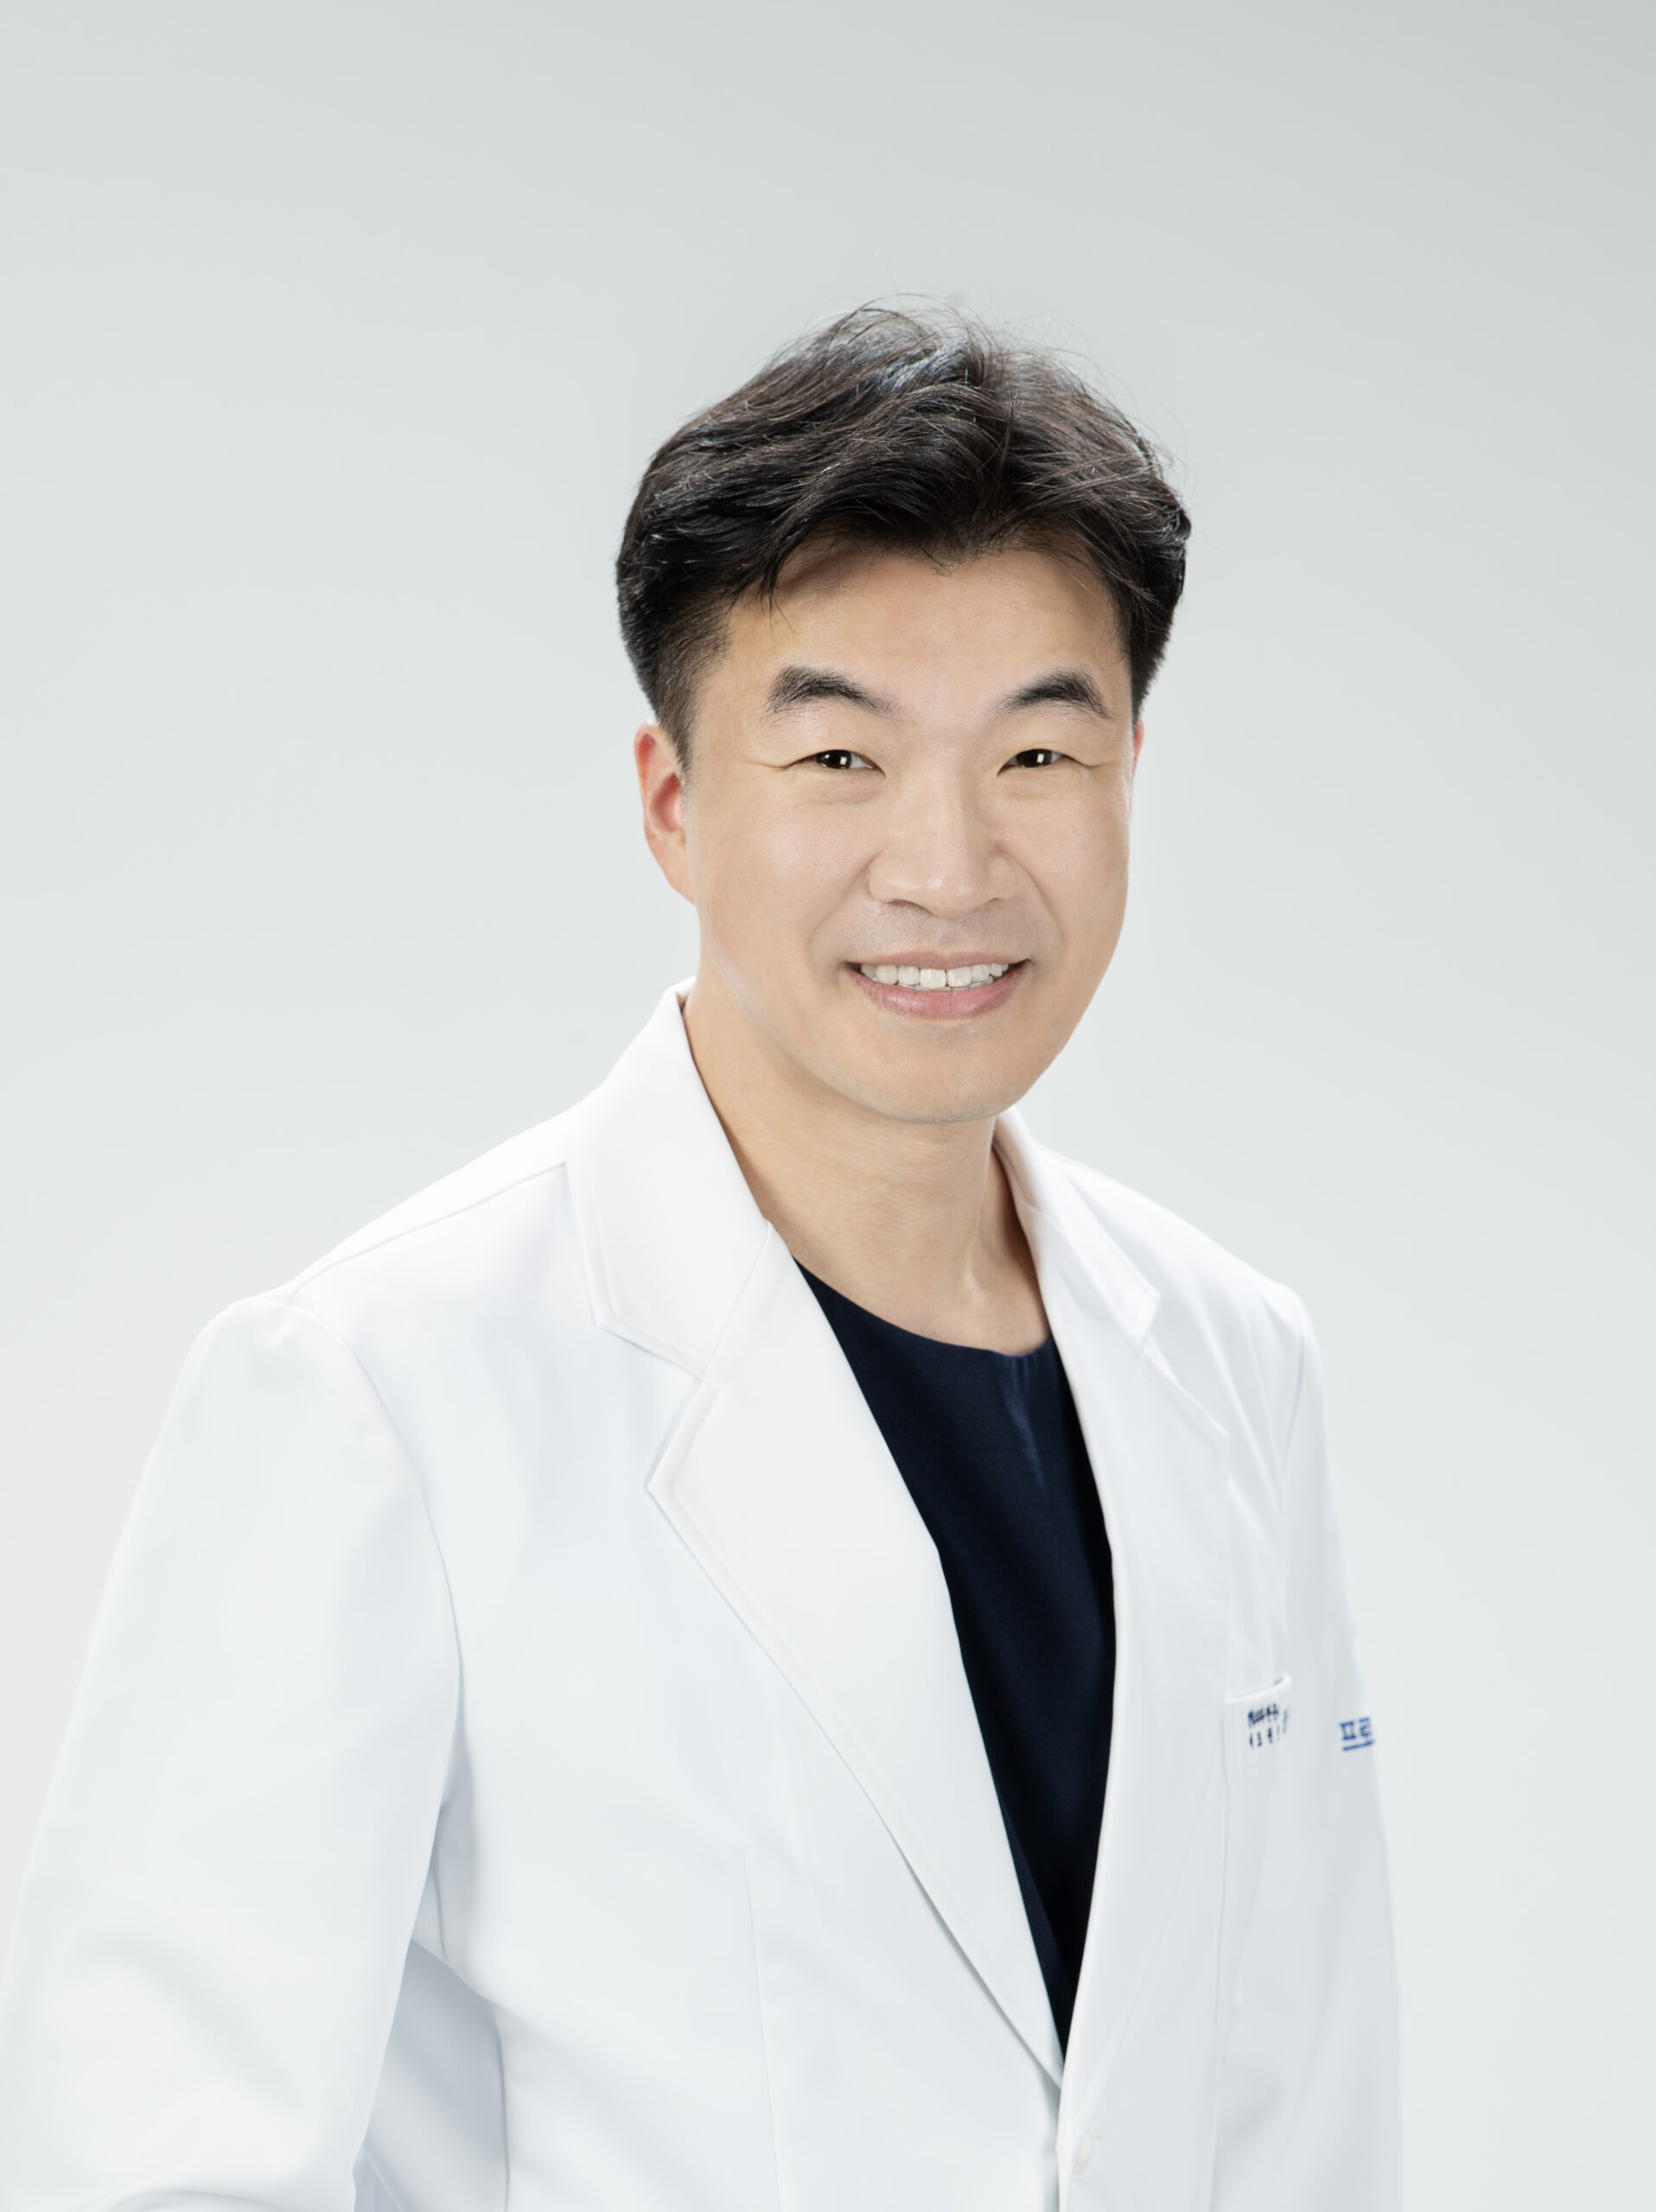

Dr. Jang Suk-hwan

Dr. Jang Suk-hwan is a highly respected orthopedic surgeon with over 15 years of experience specializing in shoulder, elbow, and sports-related injuries. As an internationally trained expert in sports medicine and orthopedic ultrasound, he has dedicated his career to providing cutting-edge treatments that help patients recover faster and regain mobility.

Whether you’re recovering from an injury, managing a chronic condition, or seeking to improve your athletic performance, Dr. Jang is here to support you every step of the way.